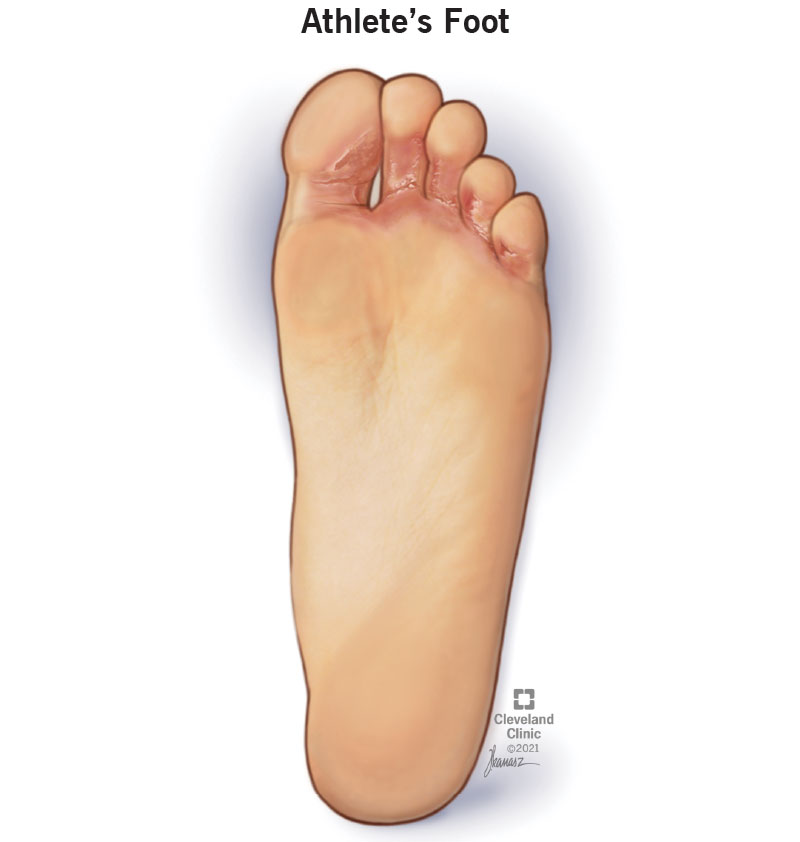

Had these on the bottom of my feet for the last two years or so shop, Foot Psoriasis Causes Symptoms and Treatment shop, Itching of the Feet 9 Common Causes shop, Scaling Skin Pictures Causes Diagnosis and Treatment shop, Hyperkeratosis Causes symptoms and treatment shop, Pitted Keratolysis Condition Treatments and Pictures for Adults shop, Why Are My Feet Peeling My FootDr shop, Juvenile Plantar Dermatosis American Osteopathic College of shop, Understanding Peeling Feet From Causes to Self Care Tips Sol shop, Dry Skin Causes Symptoms and Treatment for Your Feet shop, Dead Skin Under Feet Causes Symptoms And Treatment shop, Had these on the bottom of my feet for the last two years or so shop, Tips for Managing Foot Psoriasis Everyday Health shop, Juvenile Plantar Dermatosis Condition Treatments and Pictures for shop, Soles of feet also showed more intense spots and got erythematous shop, Itchy Feet Causes and Cures Part 1 Podiatry HQ shop, Itching of the Feet 9 Common Causes shop, Corns and calluses NHS shop, 4 Common Foot Skin Problems Treatments Foot and Ankle Group shop, Foot Calluses Your Questions Answered Dr. Scholl s shop, I m a podiatrist here s what your feet say about your health shop, How to Get Rid of Rough Dry Skin at the Bottom of Your Feet Dry shop, Foot Health Do you feel like you re walking on glass You might shop, Treatment And Prevention For Cracked Dry Heels Heel Fissure shop, 5 Reasons Why Your Feet May Be Dry Precision Foot and Ankle Centers shop, Dry Skin Dr. Alice Wang shop, Plantar Callus Bottom of Feet Removal Treatment Vs. Plantar Wart shop, How To Remove Dead Skin From The Feet My FootDr shop, What Causes Peeling Feet Why is the Skin Peeling on my Feet Buoy shop, 7 Types of Foot Rashes How to Treat Them Causes of Foot Rash shop, Get Rid of Dry Ashy or Dead Skin on Your Feet shop, Psoriasis on feet Symptoms causes and treatment shop, Little round circles and flaking skin FootCare by Nurses shop, Four Types of Eczema and How They Affect the Feet Westfield Foot shop, What Is Athlete s Foot How Do You Treat It shop, Dangers Of Dry Cracked Heels Southlake Style Southlake s shop, How Do You Get Rid Of Dark Spots On The Toes My FootDr shop, Footlogix Rough Skin on Foot Causes and Treatment shop, Eczema On Feet Symptoms Causes And Treatment Bodewell shop, How To Treat Dry Feet Advice For Dry Feet NIVEA shop, 5 Things Your Feet Are Telling You About Your Health shop, Calluses and Corns Foot and Ankle Specialists shop, Dry Skin Patches Causes Symptoms and More shop, How Hyperkeratosis Can Affect Your Feet Footfocus Podiatry shop, Why does skin peeling occur on the feet shop, Juvenile Plantar Dermatosis Condition Treatments and Pictures for shop, Foot Rash Causes Symptoms Treatment shop, Eczema on feet Types symptoms causes and more shop, 10 Subtle Signs of Disease Your Feet Can Reveal Fort Worth shop, Eczema On Feet Symptoms Causes And Treatment Bodewell shop.

Had these on the bottom of my feet for the last two years or so shop, Foot Psoriasis Causes Symptoms and Treatment shop, Itching of the Feet 9 Common Causes shop, Scaling Skin Pictures Causes Diagnosis and Treatment shop, Hyperkeratosis Causes symptoms and treatment shop, Pitted Keratolysis Condition Treatments and Pictures for Adults shop, Why Are My Feet Peeling My FootDr shop, Juvenile Plantar Dermatosis American Osteopathic College of shop, Understanding Peeling Feet From Causes to Self Care Tips Sol shop, Dry Skin Causes Symptoms and Treatment for Your Feet shop, Dead Skin Under Feet Causes Symptoms And Treatment shop, Had these on the bottom of my feet for the last two years or so shop, Tips for Managing Foot Psoriasis Everyday Health shop, Juvenile Plantar Dermatosis Condition Treatments and Pictures for shop, Soles of feet also showed more intense spots and got erythematous shop, Itchy Feet Causes and Cures Part 1 Podiatry HQ shop, Itching of the Feet 9 Common Causes shop, Corns and calluses NHS shop, 4 Common Foot Skin Problems Treatments Foot and Ankle Group shop, Foot Calluses Your Questions Answered Dr. Scholl s shop, I m a podiatrist here s what your feet say about your health shop, How to Get Rid of Rough Dry Skin at the Bottom of Your Feet Dry shop, Foot Health Do you feel like you re walking on glass You might shop, Treatment And Prevention For Cracked Dry Heels Heel Fissure shop, 5 Reasons Why Your Feet May Be Dry Precision Foot and Ankle Centers shop, Dry Skin Dr. Alice Wang shop, Plantar Callus Bottom of Feet Removal Treatment Vs. Plantar Wart shop, How To Remove Dead Skin From The Feet My FootDr shop, What Causes Peeling Feet Why is the Skin Peeling on my Feet Buoy shop, 7 Types of Foot Rashes How to Treat Them Causes of Foot Rash shop, Get Rid of Dry Ashy or Dead Skin on Your Feet shop, Psoriasis on feet Symptoms causes and treatment shop, Little round circles and flaking skin FootCare by Nurses shop, Four Types of Eczema and How They Affect the Feet Westfield Foot shop, What Is Athlete s Foot How Do You Treat It shop, Dangers Of Dry Cracked Heels Southlake Style Southlake s shop, How Do You Get Rid Of Dark Spots On The Toes My FootDr shop, Footlogix Rough Skin on Foot Causes and Treatment shop, Eczema On Feet Symptoms Causes And Treatment Bodewell shop, How To Treat Dry Feet Advice For Dry Feet NIVEA shop, 5 Things Your Feet Are Telling You About Your Health shop, Calluses and Corns Foot and Ankle Specialists shop, Dry Skin Patches Causes Symptoms and More shop, How Hyperkeratosis Can Affect Your Feet Footfocus Podiatry shop, Why does skin peeling occur on the feet shop, Juvenile Plantar Dermatosis Condition Treatments and Pictures for shop, Foot Rash Causes Symptoms Treatment shop, Eczema on feet Types symptoms causes and more shop, 10 Subtle Signs of Disease Your Feet Can Reveal Fort Worth shop, Eczema On Feet Symptoms Causes And Treatment Bodewell shop.